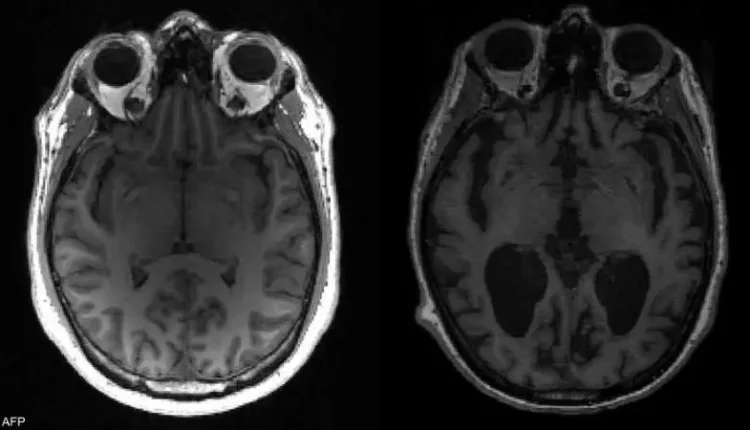

وأجرى زاري وزملاؤه اختبارات على 140 ألف خلية من 76 دماغا، وتوصلوا إلى أن أدمغة الذين ماتوا وهم يعانون ألزهايمر كانت لديهم مستويات عالية من لويحات “بيتا أميلويد” والبروتين “تاو”، التي تراكمت في الدماغ.

وبالمحصلة، أكد العلماء أن الأدوية التي تستهدف مثل هذه الخلايا في الدماغ، يمكن أن تقلل من آثار تراكم مثل تلك العناصر، وإبطاء تقدم أعراض ألزهايمر.